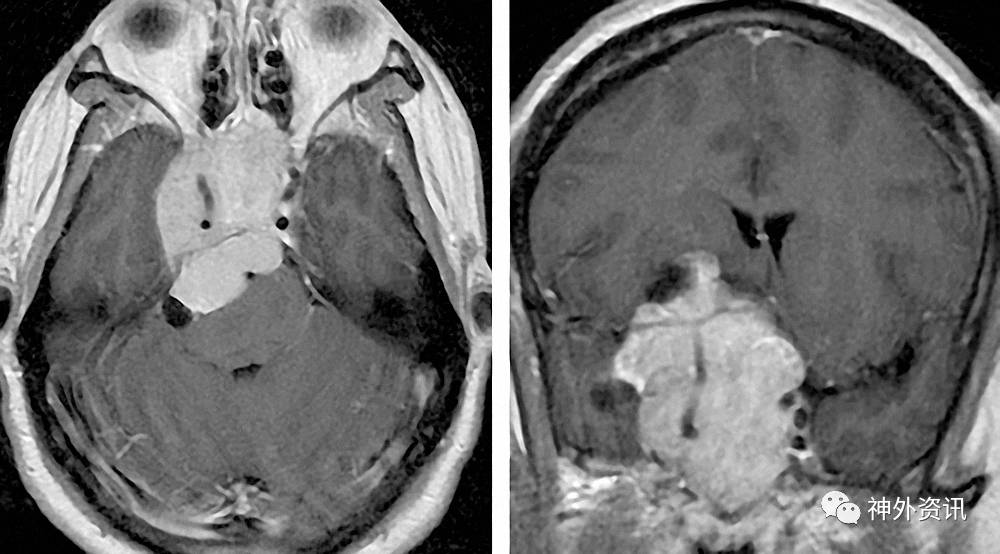

任何鞍旁病变的患者均需行垂体轴激素水平的评估,避免围术期垂体功能储备不足。血清泌乳素、皮质醇和甲状腺素水平尤其重要。围术期糖皮质激素的常规应用可避免低皮质醇血症的发生,而本身已存在的甲状腺功能减退,可在手术后骤然进展。以下是笔者曾经遇到的偏中线生长的极不对称的泌乳素腺瘤。

图4. 不典型的泌乳素腺瘤伴癫痫患者。病灶呈偏侧生长,影像上表现类似脑膜瘤。该病例印证了术前泌乳素水平评估对避免不必要的手术的重要性。